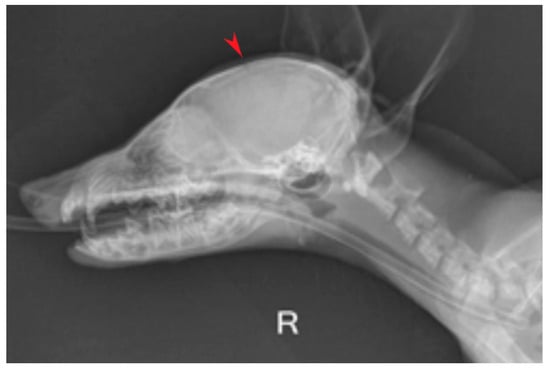

2. Case Description

- Raposo, M.; Añor, S.; Verdés, J.; Soler, V.; Martorell, J. Diagnosis and Treatment of Congenital Hydrocephalus in a Red Fox (Vulpes vulpes) with Seizures. Vet. Rec. Case Rep. 2022, 10, e310. [Google Scholar] [CrossRef]